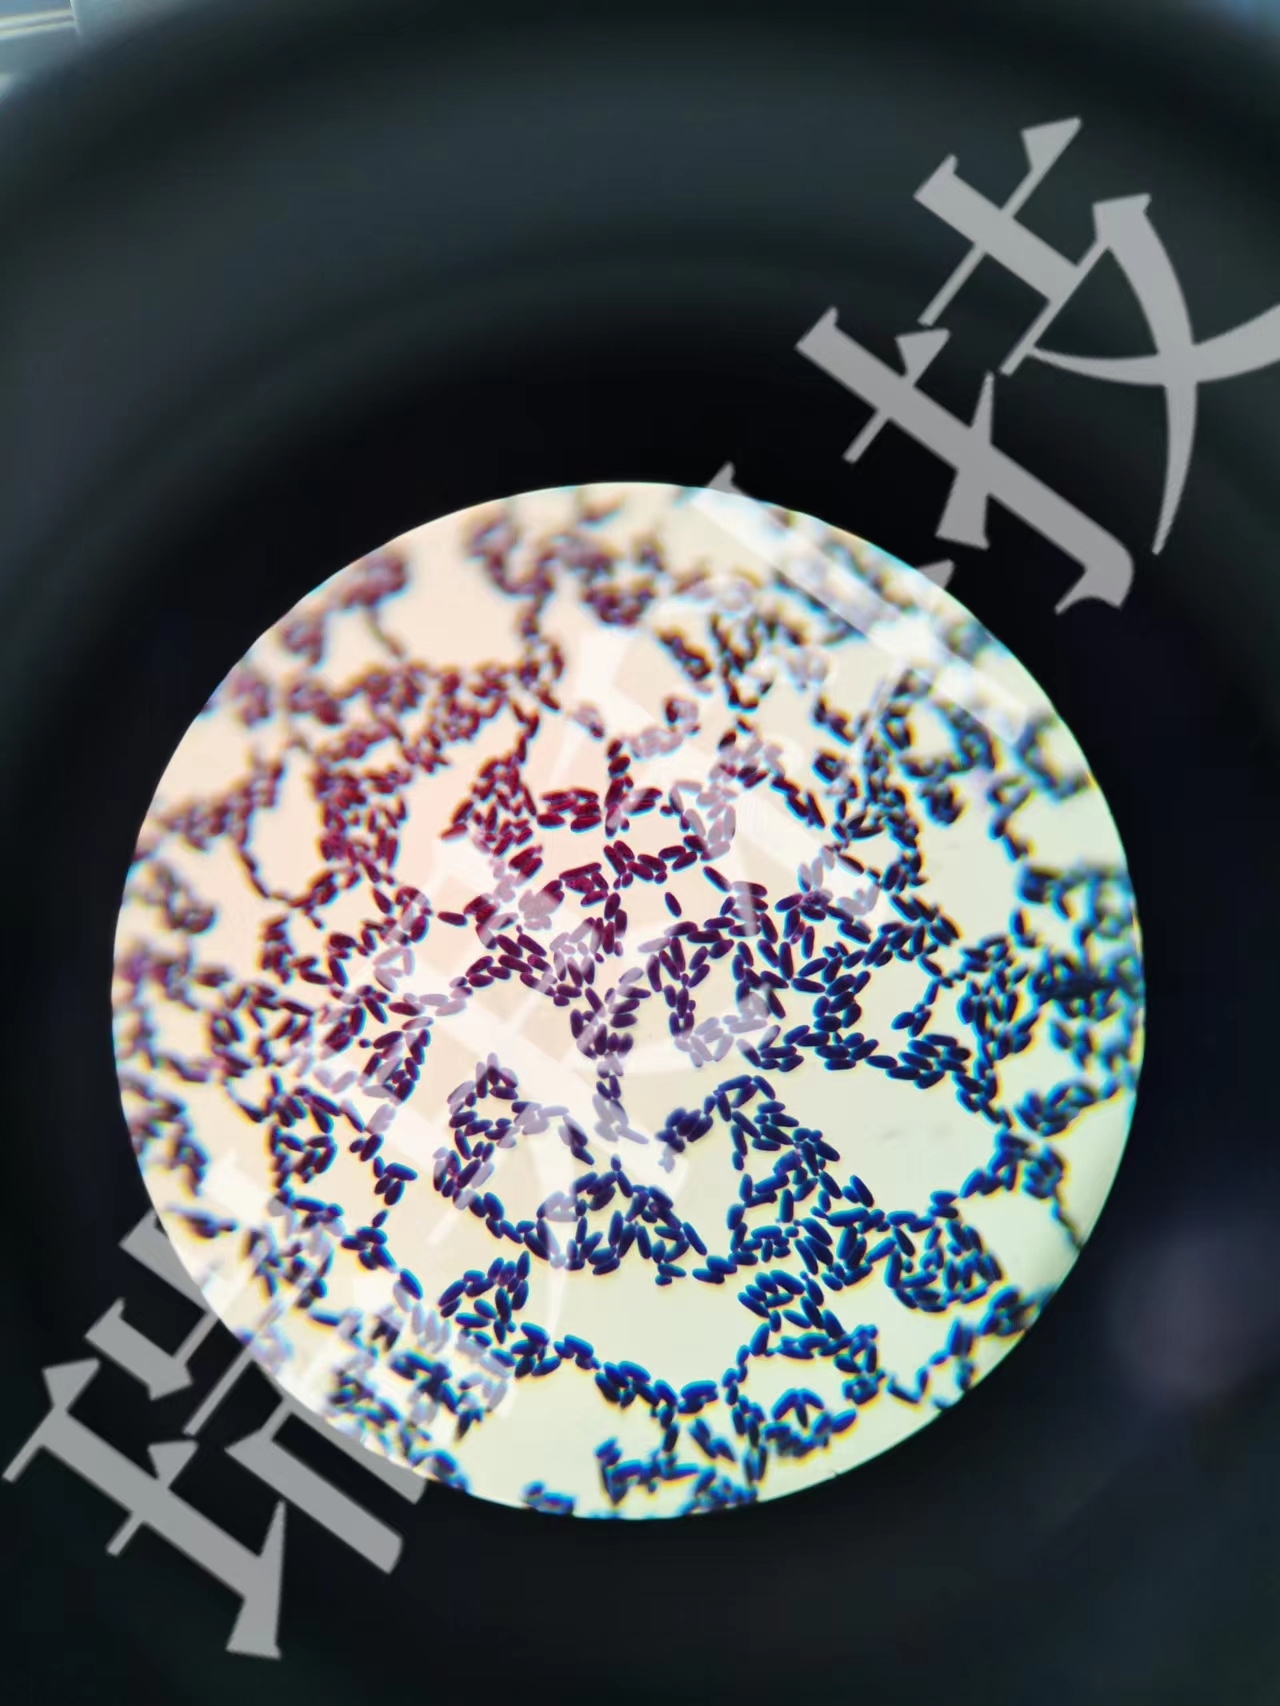

刚果红染色:刚果红染色法特指纤维素的染色法,刚果红能把纤维素染成红色复合物,对纤维二塘和葡萄糖无作用,可用此来鉴别纤维素或纤维素分解菌的分解作用。